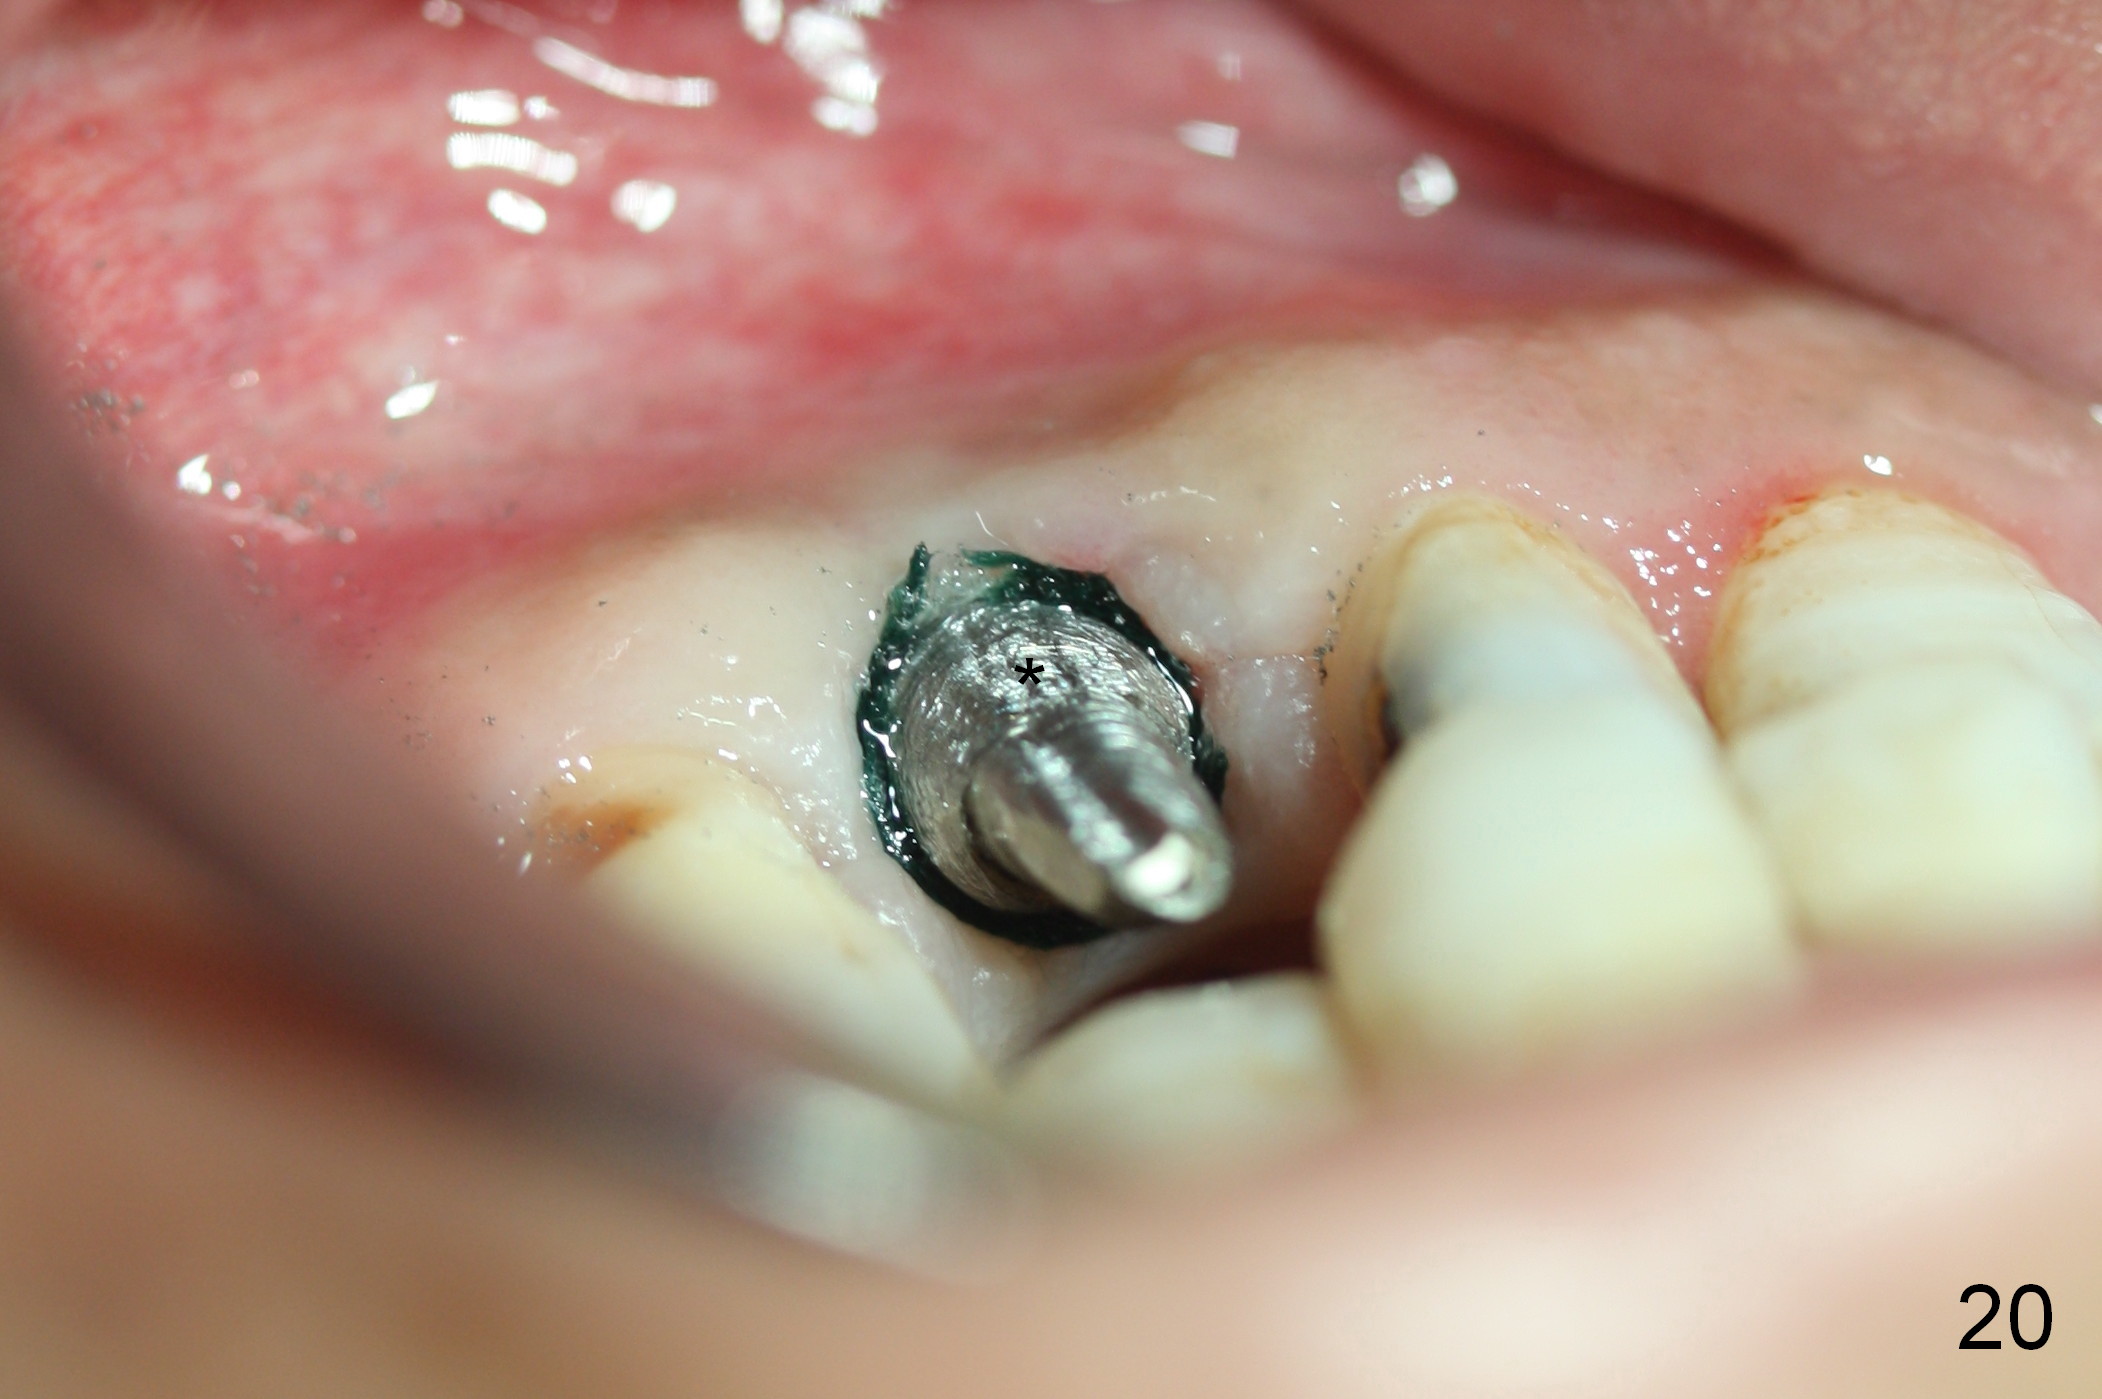

One and a half months later (3 months postop), the patient returns for final crown impression. The buccal gingiva has grown coronally (Fig.17 arrow). The implant appears to have osteointegrated (Fig.18). The buccal plate has become concave (Fig.19 arrowheads). To maintain the gingival level, the buccal portion of the implant/abutment (Fig.19 *) is going to be reduced (Fig.20 *). The margin of the definitive restoration will be at the prep margin and thin so that the gingiva is expected to continue to be growing coronally after cementation.